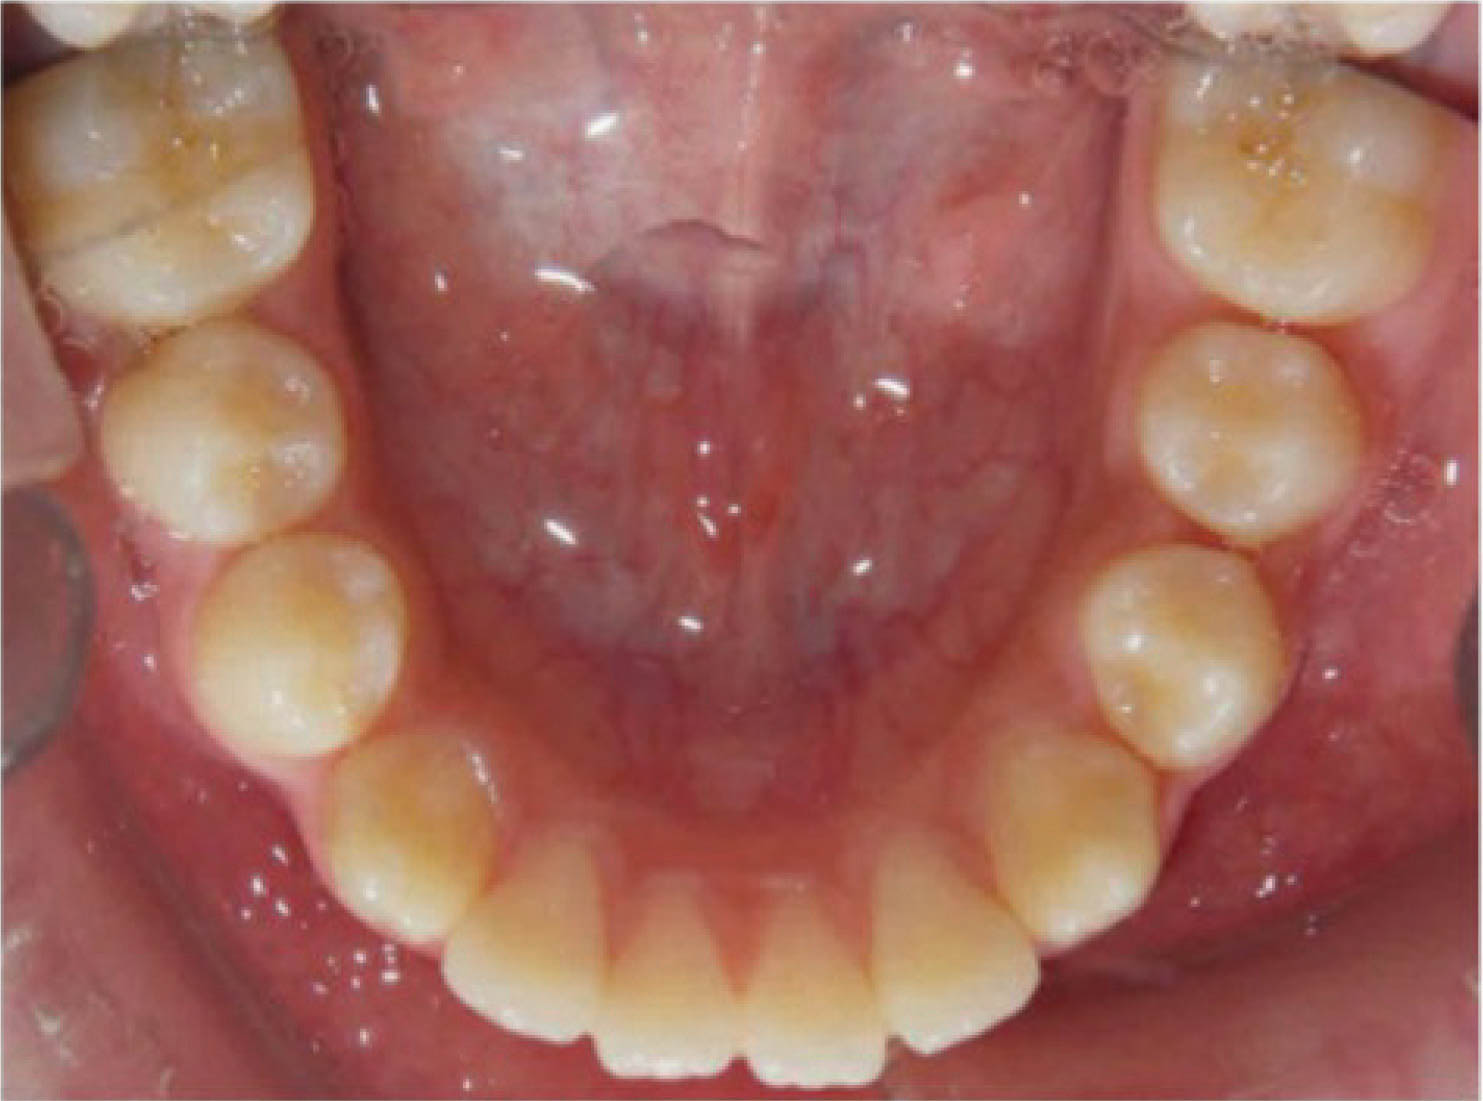

بیمار دیگر (شکلهای 50-6 الی 52-6): لترال چپ بالا را ندارد. هدف دیستاله نمودن کانین چپ بالا و هدایت آن تا رسیدن به رابطه کلاسI کانینی و نهایتاً قرار دادن یک ایمپلنت در ناحیه لترال است. اگر به OPG او نگاه بندازید، میبینید که لترال چپ بالا وجود ندارد و لترال راست بالا هم peg shape است.

: باید به لابراتوار بگوییم که تیپ دیستالی بیشتر به ریشه کانین چپ بالا بدهد. این زاویه بیشتر برای بیومکانیک کار است تا دندانها تیپ نشوند. باید در این بیمار هم همین کار را انجام داد. از آنجایی که قرار است کانین چپ بالا دیستالی بشود، احتمال دیستالی شدن تاج و مزیالی شدن ریشه وجود دارد. این حالت نه تنها مدنظر نیست، بلکه فضای کافی هم برای قرار دادن ایمپلنت به ما نمیدهد. بنابراین باید زاویه بیشتری به ریشه بدهیم تا در نهایت یک حرکت بادیلی داشته باشیم.

در OPG نهایی، کانین راست بالا در جایگاه صحیح است و فضا کافی برای ایمپلنت هم به وجود آمده است (کل درمان ۲۰ ماه به طول کشید). در این بیماران، باید حتماً درمان اضافه را در طراحی کامپیوتری در نظر بگیرید تا حرکتها بادیلی بشوند.

شکل 50-6

شکل 51-6

شکل 52-6